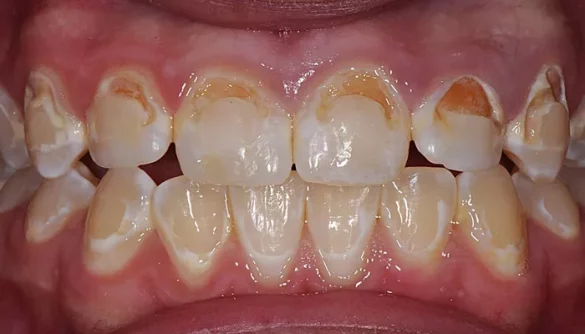

3. Staining of the Teeth

As pre-cavities progress, the enamel may begin to stain more easily. This is because the weakened enamel is more porous, allowing food and drink particles to penetrate the tooth. Staining often occurs in the early stages of decay, especially if the person consumes a lot of staining foods, such as coffee, tea, or sugary drinks.

In the case of pre-cavities, the staining may not be uniform. Instead, it may appear as spots or patches of discoloration that stand out against the surrounding healthy enamel. If you notice unusual stains on your teeth, it could be a sign that the enamel is starting to break down, and pre-cavities are forming.

5. Dark Spots on the Teeth

While white spots are often the first sign of pre-cavities, they may eventually turn into dark spots. This happens as the enamel continues to demineralize, and the tooth begins to discolor. These dark spots may appear brown, black, or gray, and they may be an indication that the decay is worsening. Dark spots often indicate that the enamel has become severely weakened, and it is more likely that a full cavity will develop if the decay is not treated promptly.